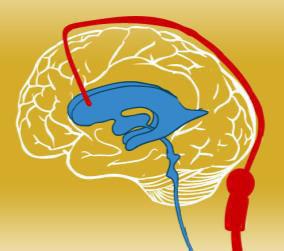

• Structurally similar to the neurotransmitter GABAAgonist action (GABAb receptor)Main action on primary afferent neurons of the spinal cord, possible action on cerebral 5MA receptors

Stretch reflex inibition

Lower spasticity

• Hydrophilic drugDaily dose 60-120mgSide effects at low plasma levelsBBB blocks passage (30-60mg oral = 12–

96 mg/ml CSF)Response to oral therapy not predictive

• High CSF concentration (501500 mcg/day = 30-1240 ng/ml CSF)Steady state in 24-48hLow plasma levels (5 ng/ml)Half-life

180 minutesHigher concentration at lumbar level (lumbar:cisterna magna = 4:1)Effective dose 100-1000 times lower

Age > 4 yearsAdequate body weight > 20kgAdequate

subcutaneous tissue